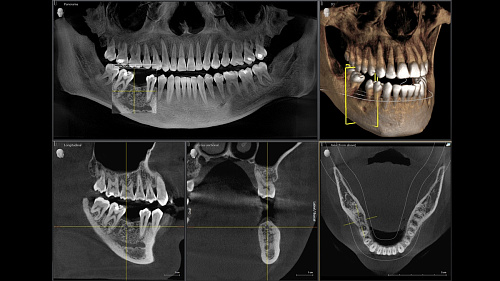

Диагностика последнего поколения, идеально решающая задачи рентгеновского обследования независимо от размеров клиники. Поля изображения зависят от определенной клинической картины, поэтому специалистам так удобно работать с ORTHOPHOS SL 3D. Данная установка делает объёмные картинки для одиночной реставрации в 3D качестве полностью всей челюсти такого размера, которого требуется.

Планирование одиночной реставрации, эндодонтические исследования и пр. – для этого специалист может выбрать объёмные варианты 8 х 8 см или 11 х 10 см, также предлагается объём 5 х 5,5 см. Снимки в HD-качестве, стандартные настройки или выбор объёма обследования в зависимости от диагноза — всё это врач получает в отличном качестве, а для пациента излучение в районе исследования минимально.

Модернизированный сенсорный экран Easypad с понятным и удобным интерфейсом позволяет выставить наилучшие параметры контрастности и разрешения. Систематизация данных по диагностике становится значительно удобнее и проще с ПО обработки изображений SIDEXIS 4, ORTHOPHOS.

1. Двух-и трёхмерные снимки совмещаются в одной программе

2. В одном окне можно сравнивать разные 3D-результаты

3. Считанные минуты уходят на просмотр анамнеза пациента.